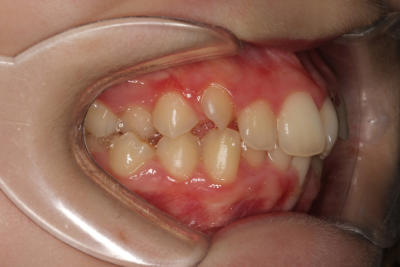

Crowding – Child case